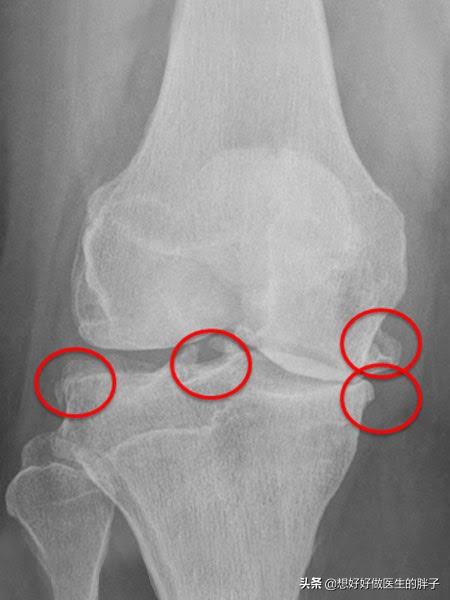

为什么有的人将骨赘称之为骨刺呢?就是因为有一些骨赘是突出骨骼范围之外的,其实这些骨赘比较小的时候,是不会对周边的软组织产生刺激和损伤的,但是如果当骨刺比较大以后,就有可能影响到周边的软组织、肌腱以及骨结构,从而产生疼痛、肿胀以及屈伸受限等症状。(下图的膝关节x线,患者就可能产生屈伸障碍、关节后方的疼痛或不适)